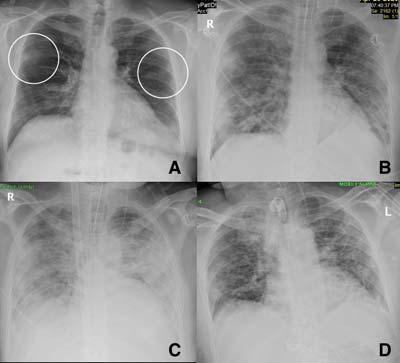

Most common findings seen on imaging of COVID-19 patients are ground-glass opacity and consolidation with a preferential involvement of lower lobes and bilateral disease5-7,10-13

Ground Glass Opacities (GGO):

On CXR, GGO appears as an area of hazy increased

lung opacity within which margins of pulmonary vessels may be difficult to see14. These are much better seen on Computed Tomography (CT) and are less opaque compared to consolidation (Fig 1). When associated with reticular opacities, the detection becomes easier. Hazy opacities on CXR can also be diffuse making its identification challenging10 (Fig 2). In patients with proven COVID-19, GGO was seen in 20-33% of patients at presentation1113,15. Normal lung parenchyma may mimic areas of GGO in poorly taken films and/or due to overlying soft tissues such as prominent breast tissue13

Consolidation :

Consolidation is seen as an area of homogeneous opacification in the lung parenchyma with obscuration of the vessel and airway walls14. In COVID-19 and other viral pneumonias, there is multi-lobar and often bilateral involvement (Fig 3). This is in contrast to the typical unilateral lobar distribution of bacterial pneumonia16. One of the early studies from China had reported the presence of consolidation in all CXR’s at presentation17. On studies published subsequently, consolidation was found in varying frequency, ranging from 5-80%11-13 15

Distribution :

Classical distribution seen in most of the patients is that of bilateral involvement with lower lobe predominance. Peripheral distribution was more common than central involvement12,13,17 (Fig 4). In a more recent study by Weinstock et al15, lower lobe predominance and peripheral distribution was seen in about 35% of patients but bilateral involvement was only seen in 21% of cases. Diffuse distribution of lung opacities can also be seen as the disease progresses. The appearances are similar to Acute Respiratory Disease Syndrome (ARDS) patterns10 (Fig 5).

Fig 1 — CXR (A) and CT (B) images of a 45-year-old male who presented with fever and cough. He had hypoxia and leukopenia on examination and his nasal swab was positive for SARS COV-2. CXR shows bilateral blurred opacities with unclear vascular margins (white arrow) with corresponding ground glass changes in the CT (black arrows). Images reproduced with permission from Covid-19 Database of the SocietaItaliana di Radiologia Medica e Interventistica.

Fig 2 — CXR (A) and CT (B& C) images of a 50-year-old man with 6 days history of fever and dry cough. RT-PCR test was positive. CXR shows bilateral diffuse opacities, with a more opaque patch in the right lower zone (white arrow). The corresponding CT shows the true extent of the disease (black arrows). Images reproduced with permission from Covid-19 Database of the Fleischner Society.

Fig 3 — CXR images from two different patients with COVID-19 showing peripheral areas of consolidation bilaterally in A and unilaterally in B (arrows). Images reproduced with permission from Covid-19 Database of the Societa Italiana di Radiologia Medica e Interventistica.

4 — CXR of a 71-year-old man with 4 days history of shortness of breath. Classical features of hazy opacities are seen in the lower lobes bilaterally in a peripheral distribution. Image reproduced with permission from Covid-19 Database of the Fleischner Society.

Fig 5 — CXR’s of different patients with proven COVID-19 demonstrating varied appearances at the time of presentation. ANo abnormalities could be seen on CXR and the corresponding CT (not shown) was also near normal. B- Ill-defined hazy peripheral opacities seen in the left upper zone. C- Multifocal opacities were seen in the right lung on CXR at presentation. D- CXR showing extensive parenchymal infiltrates in a patient who came to the hospital in very bad respiratory distress and was found to have COVID-19 on testing.